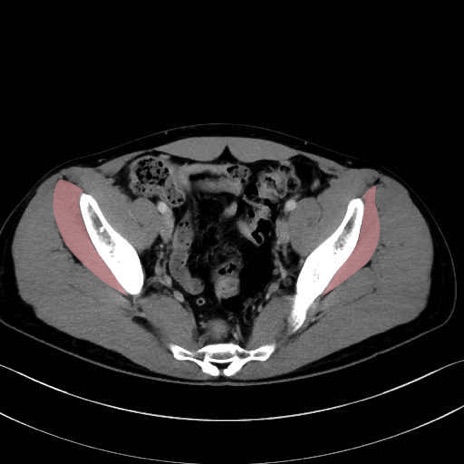

小殿筋 (Gluteus minimus)